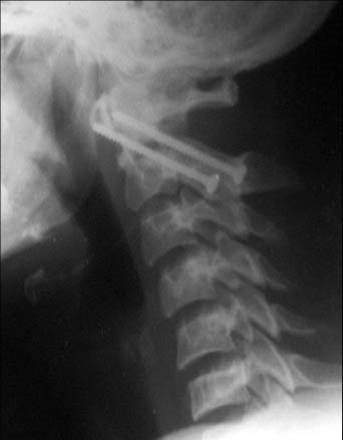

- Консервативное и оперативное лечение пациентов с дегенеративно-дистрофическими повреждениями позвоночных сегментов (остеохондроз, спондилез, спондилоартроз, грыжи и протрузии дисков), как современными транспедикулярными фиксаторами, пластинами для передней фиксации, так и динамическими системами - практически не ограничивающими физиологический объем движений;

- Оперативное и консервативное (ортезирование, корсетирование) лечение переломов и посттравматических деформаций ( в т.ч. неправильно срастающихся переломов, клиновидных деформаций, спондилопатий) с использованием систем, позволяющих при минимальной инвазивности добиться отличной реконструкции и восстановления;